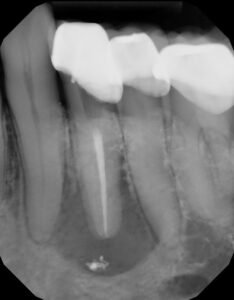

Our exam found #21 normal to percussion, normal probings and swelling on the buccal. An additional canal was suspected, so CBCT was taken for further review.

CBCT clearly shows an additional lingual canal. CBCT mapping allowed us to determine where the canal would be located and confirm that it had its own apical foramen. With greater understanding of the canal anatomy, available only through 3D imaging, we recommended non-surgical retreatment to address the missed lingual canal.

With the aid of the microscope, we were able to locate and treat the missed lingual canal.